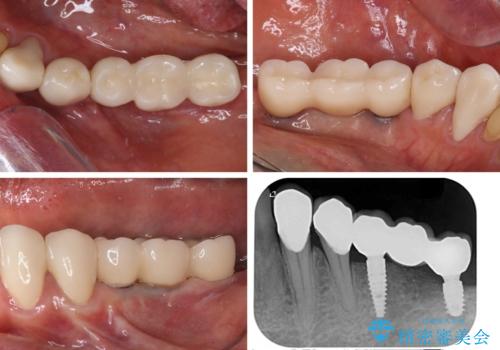

インプラント埋入後、必要以上に傷口に歯ブラシを当てすぎてしまったことで歯肉の炎症が続き、それに伴いインプラント周辺の骨が若干吸収してしまいました。それでも術後の経過は良好で、違和感や不具合なく使用できています。